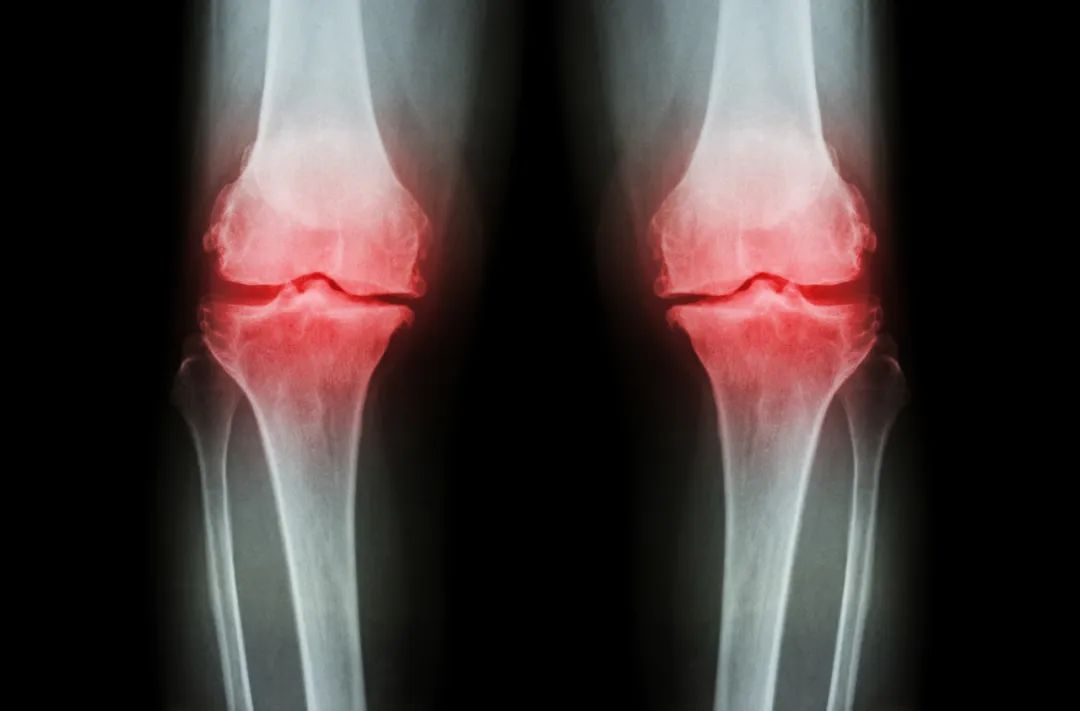

这就需要给大家补充一个知识点了,要想保护膝盖,不只是保护好上下两根梆硬的棒子骨就对了,膝盖软骨的健康也很重要。

图片

图片来源:摄图网

软骨的作用非常关键,一方面,它可以充当骨头之间的“缓冲垫”,让骨头在应对压力和冲击的时候不至于被破坏。

另一方面,它也起到润滑关节的作用,我们平时伸腿弯腿那么丝滑,膝盖软骨功不可没。

膝关节常见的疾病主要是关节炎(如骨性关节炎、类风湿关节炎)以及软组织损伤(如半月板损伤、前交叉韧带损伤)之类的。